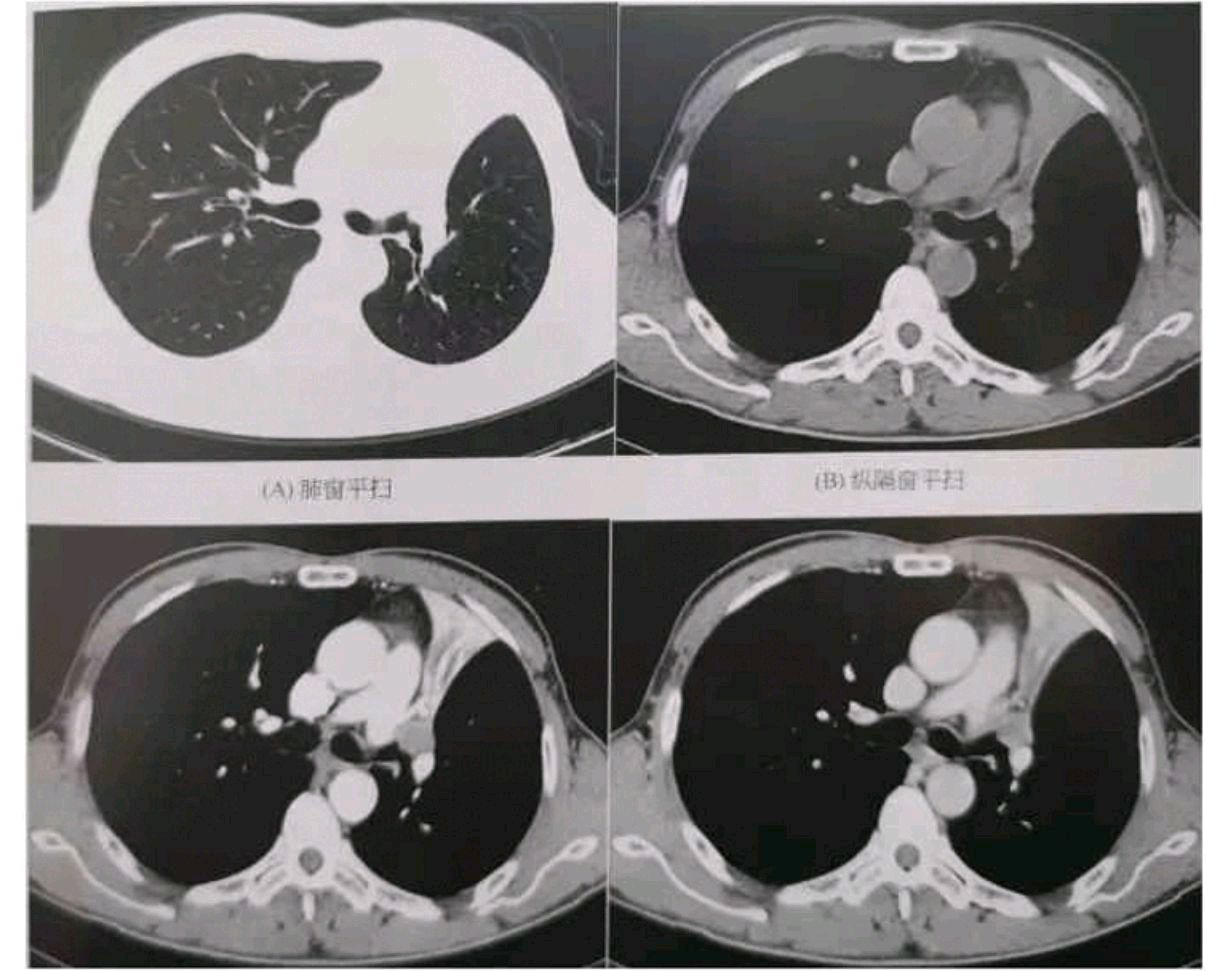

中央型肺癌ct

简述中央型肺癌特点及影像表现

影像基础知识:中央型肺癌ct表现及报告书写!